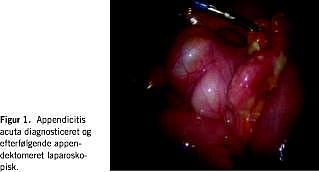

Laparoskopisk kirurgi har vist sig at medføre nedsat inflammatorisk stressrespons, kortere hospitalisering og forbedret rekonvalescens i forhold til konventionel kirurgi. Laparoskopien vinder derfor frem ved flere og flere kirurgiske tilstande [1]. Alle kirurger bør beherske laparoskopisk teknik [2, 3]. Kirurgisk oplæring har været baseret på mesterlære, hvor den åbne apppendektomi (ÅA) har været anvendt som oplæringsoperation. Den diagnostiske laparoskopi (DL) har været foreslået som oplæringsoperation i basal laparoskopisk teknik [3, 4]. DL er bl.a. relevant ved mistanke om appendicitis acuta, idet den kliniske diagnose appendicitis er ret upålidelig, således findes kun korrekt diagnose hos ca. 70%. Med afsæt i ovenstående ønskede vi på Kirurgisk Gastroenterologisk Afdeling D, Amtssygehuset i Glostrup, at indføre DL ved klinisk mistanke om appendicitis acuta og at foretage laparoskopisk appendektomi (LA) ved peroperative tegn på appendicitis (Figur 1).